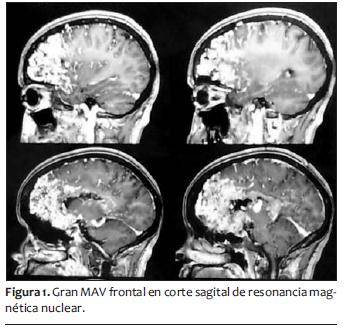

Presentaba antecedentes quirúrgicos anestésicos de cesárea de coordinación hace 3 años, con anestesia peridural sin incidentes y antecedentes personales de epilepsia sintomática secundaria a MAV cerebral gigante frontal izquierda diagnosticada 12 años atrás, sin indicación quirúrgica por alto riesgo, en tratamiento con clonazepan 4 mg/día y valproato, que suspendió en el embarazo. La resonancia nuclear magnética informaba voluminoso nido de MAV a nivel frontal izquierdo con gliosis locoregional asociada (figuras 1 y 2). Voluminosos troncos de drenaje superficial y profundo con dilataciones venosas. Angioma cavernoso a nivel frontal subcortical del lado derecho paraventricular.